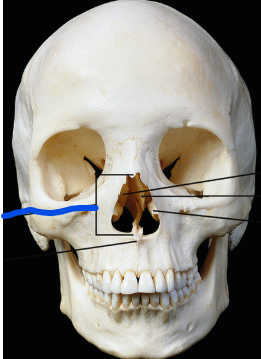

Name the structure

Anterior nasal aperture